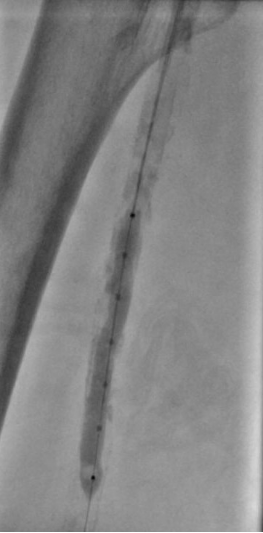

5. 选择6*60mm Shockwave冲击波球囊处理股腘动脉

本例患者股浅动脉重度闭塞,股浅远端重度钙化病变近收肌管,利用Shockwave冲击波球囊获得满意的管腔准备后联合使用DES,为保障远期通畅植入支架,支架膨胀形态理想。

我国患者股浅动脉又多以长段闭塞病变为主,为保障远期通畅率,支架的植入往往不可避免,此时如何优化支架膨胀则至关重要。利用“聚焦式”的冲击波能量作用于重度钙化环最薄弱处,在低压下安全打开钙化斑块,尤其是限制血管床弹性的环形钙化,可有效增加管腔顺应性,减少弹性回缩。